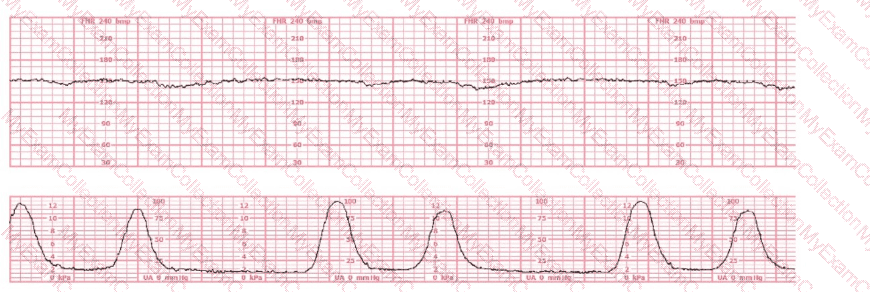

A 30-year-old woman (G2P0) is experiencing preterm labor at 26-weeks gestation. She is receiving magnesium sulfate for neuroprotection. Her external fetal monitoring tracing over the past 30 minutes is shown. The next step would be to: